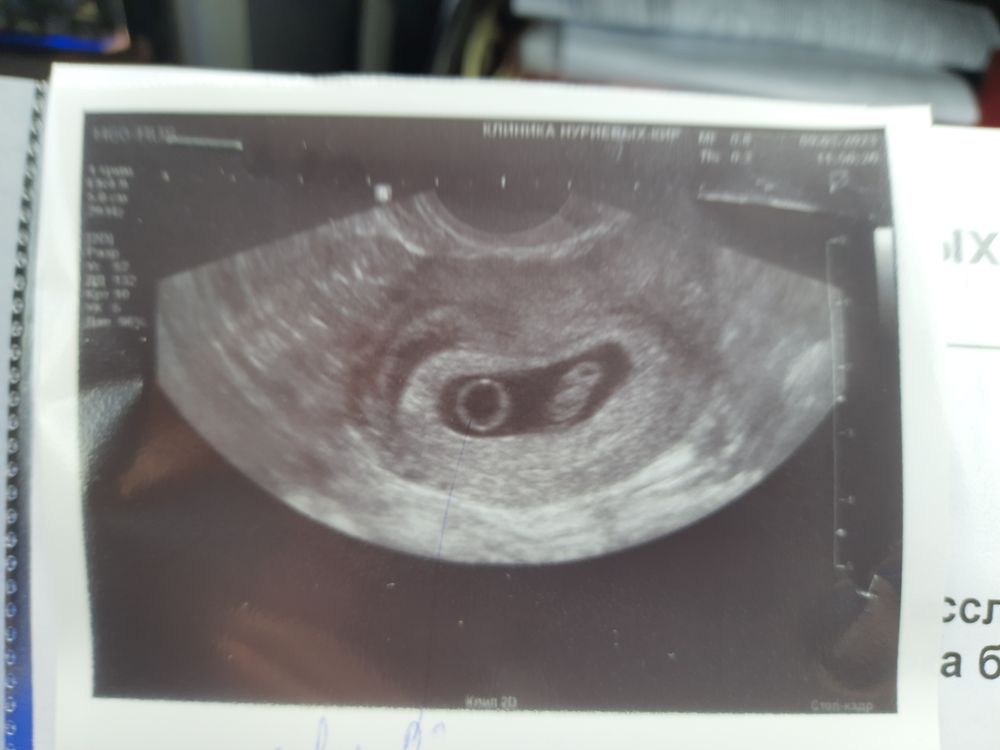

23 дпп узи